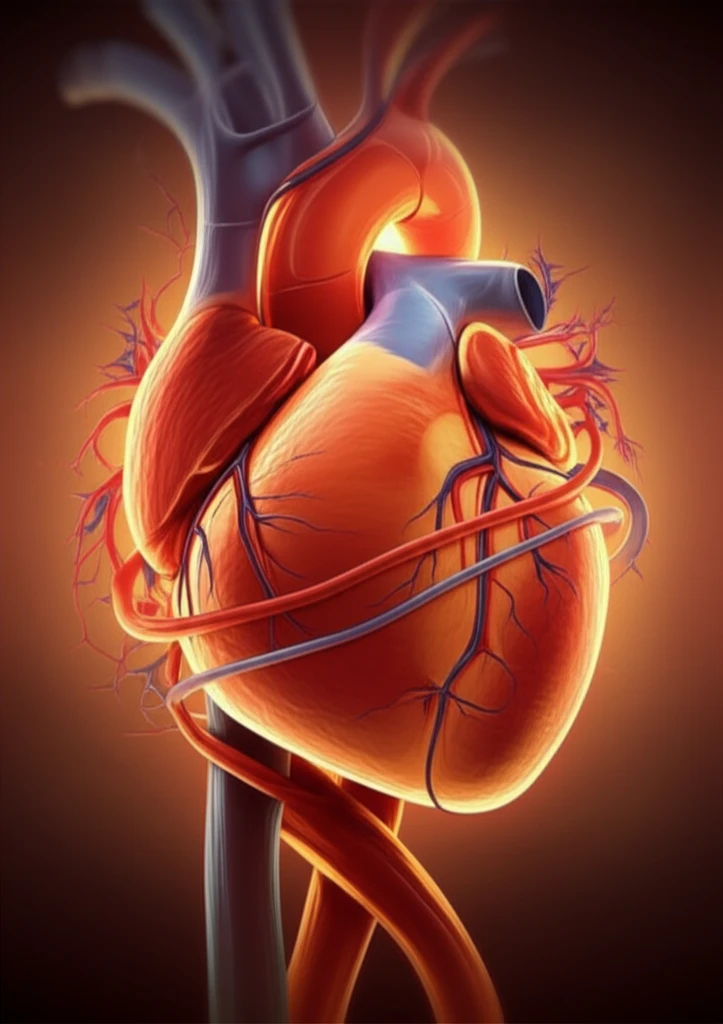

For individuals grappling with severe left ventricular (LV) dysfunction, a condition where the heart struggles to pump blood effectively, coronary artery bypass surgery presents a significant challenge. But, the evolution of surgical methods, particularly the rise of off-pump coronary artery bypass (OPCAB) surgery, offers a beacon of hope.

OPCAB has emerged as a compelling alternative to traditional bypass surgery, which relies on cardiopulmonary bypass machines. OPCAB allows surgeons to operate on a beating heart, reducing the risks associated with stopping and restarting the heart. Furthermore, studies suggest that using bilateral internal thoracic arterial grafts, which utilize arteries from the chest wall, provides superior long-term outcomes compared to single grafts.

Although OPCAB with bilateral internal thoracic arterial grafting shows promise for patients, understanding the specific outcomes remains crucial. This article will explore how patients with severe left ventricular dysfunction fare with this innovative surgical approach, comparing their results to those with better heart function.